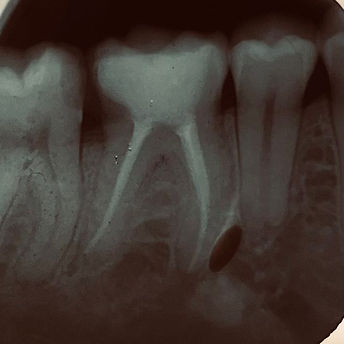

Câmera Intraoral;

Rx portatil;

Sensor rx;